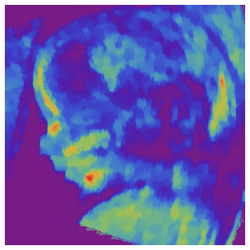

Artificially colored, showing gestational sac, yolk sac and embryo (measuring 3 mm as the distance between the + signs)